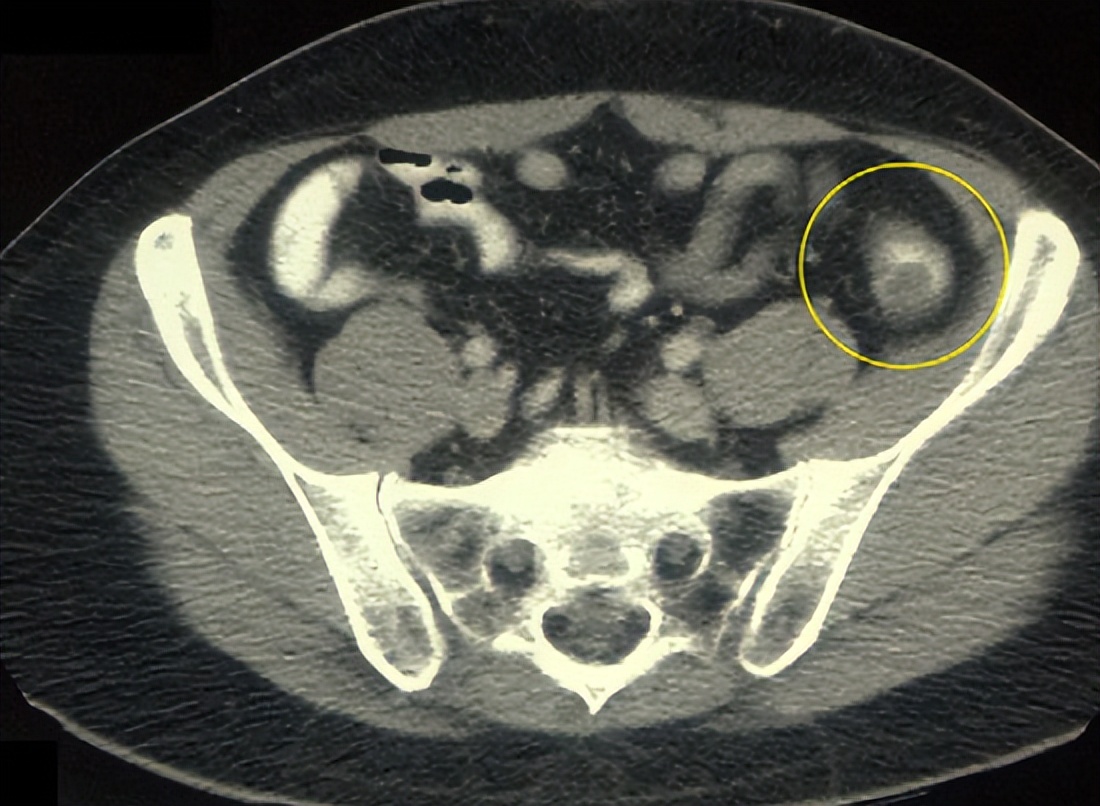

如果做肝脏超声检查,有时报告单上会描述在肝脏的某个部位有实质性占位,或者描述某个部位有囊性占位。那么什么是实质性占位,什么是囊性占位呢?

如果这个占位性病变是由实体性的组织组成的,就叫做实质性占位,如增生的肝细胞结节、血管瘤、或者肝癌等,都是实质性占位。如果这个占位性病变由液性的组织组成,就叫做囊性占位,最常见的是肝囊肿,在囊肿内充满了液体,超声检查可以显示出液体的回声。

超声检查对于鉴别实质性占位和囊性占位非常敏感,是最常用和最有效的检查手段。

一般情况下,通过肿瘤标志物和影像学检查,如增强CT、MRI、超声造影等可以把良性、恶性占位鉴别开。也有一些占位性病变很难鉴别良性、恶性,这时就需要考虑做肝穿刺活检,获得组织做病理学检查。#肝癌##超能健康团#